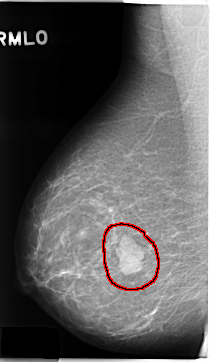

ics_version 1.0 filename C-0131-1 DATE_OF_STUDY 22 9 1995 PATIENT_AGE 48 FILM FILM_TYPE REGULAR DENSITY 1 DATE_DIGITIZED 16 1 1998 DIGITIZER LUMISYS LASER SEQUENCE LEFT_CC LINES 4776 PIXELS_PER_LINE 2712 BITS_PER_PIXEL 12 RESOLUTION 50 NON_OVERLAY LEFT_MLO LINES 4696 PIXELS_PER_LINE 2760 BITS_PER_PIXEL 12 RESOLUTION 50 NON_OVERLAY RIGHT_CC LINES 4736 PIXELS_PER_LINE 2616 BITS_PER_PIXEL 12 RESOLUTION 50 OVERLAY RIGHT_MLO LINES 4704 PIXELS_PER_LINE 2720 BITS_PER_PIXEL 12 RESOLUTION 50 OVERLAY |

FILE: C_0131_1.RIGHT_MLO.OVERLAY TOTAL_ABNORMALITIES 1 ABNORMALITY 1 LESION_TYPE MASS SHAPE LOBULATED MARGINS CIRCUMSCRIBED ASSESSMENT 5 SUBTLETY 5 PATHOLOGY MALIGNANT TOTAL_OUTLINES 1 BOUNDARY |